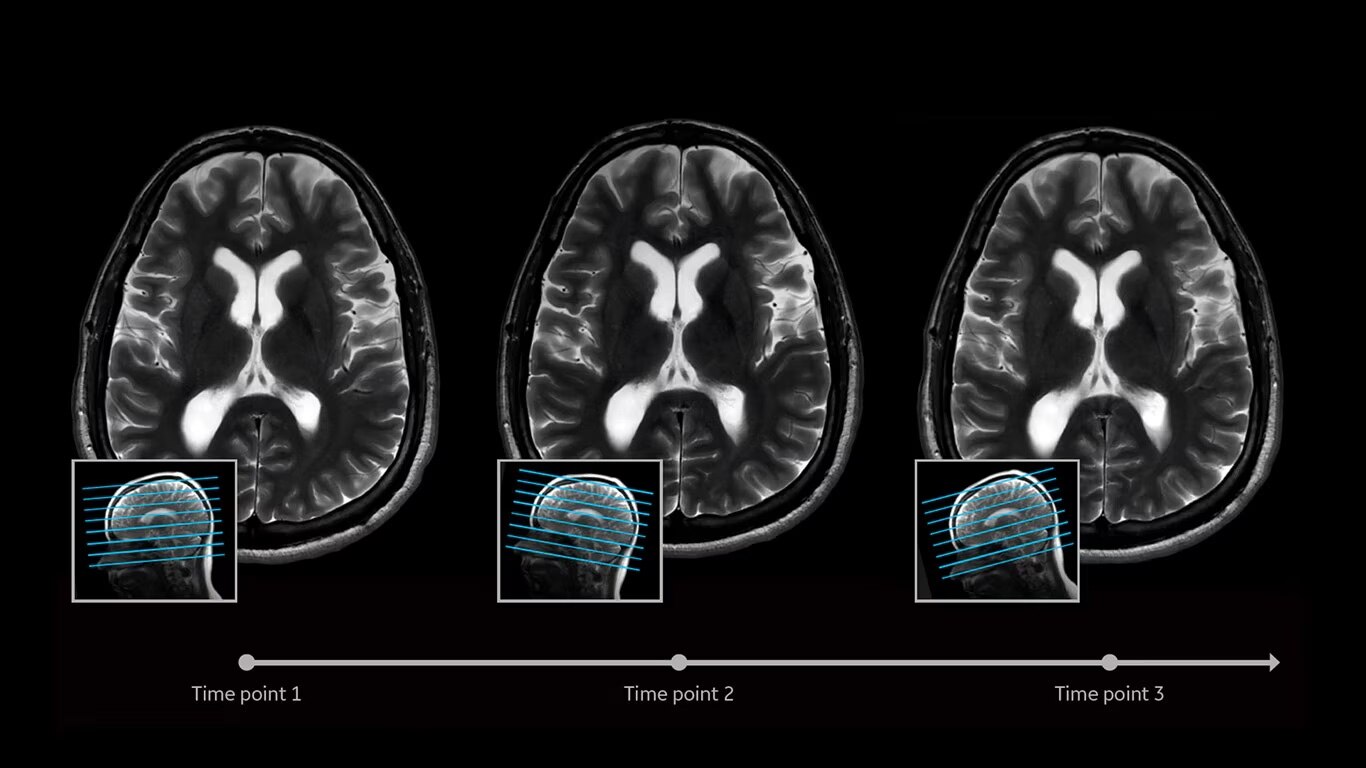

Eliminate the sources of variation by letting processes flow. AIR x™ uses deep-learning algorithms created from a database of 10's of thousands of images to automatically detect patient anatomy and prescribe MRI slices for routine and challenging neurological and knee exams, delivering consistent and quantifiable results. The automated workflow creates efficiency and reproduces steps used in planning to ensure exam consistency for same patient follow-up.

AIR x™ automatically detects patient anatomy and prescribes MRI slices for routine and challenging neurological and knee exams, delivering consistent and quantifiable results.

Deliver consistent MRI slice placements across multiple clinical time points, with a deep-learning algorithm that provides efficiency and time savings.